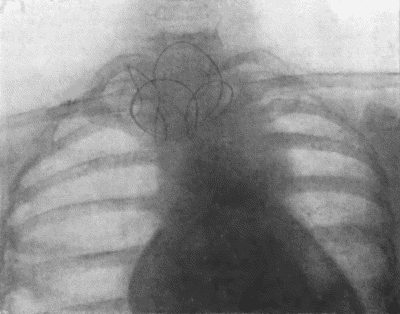

73.Radiogram of Innominate Aneurysm after Treatment by Moore-Corradi method 309

74.Thoracic Aneurysm threatening to rupture 313